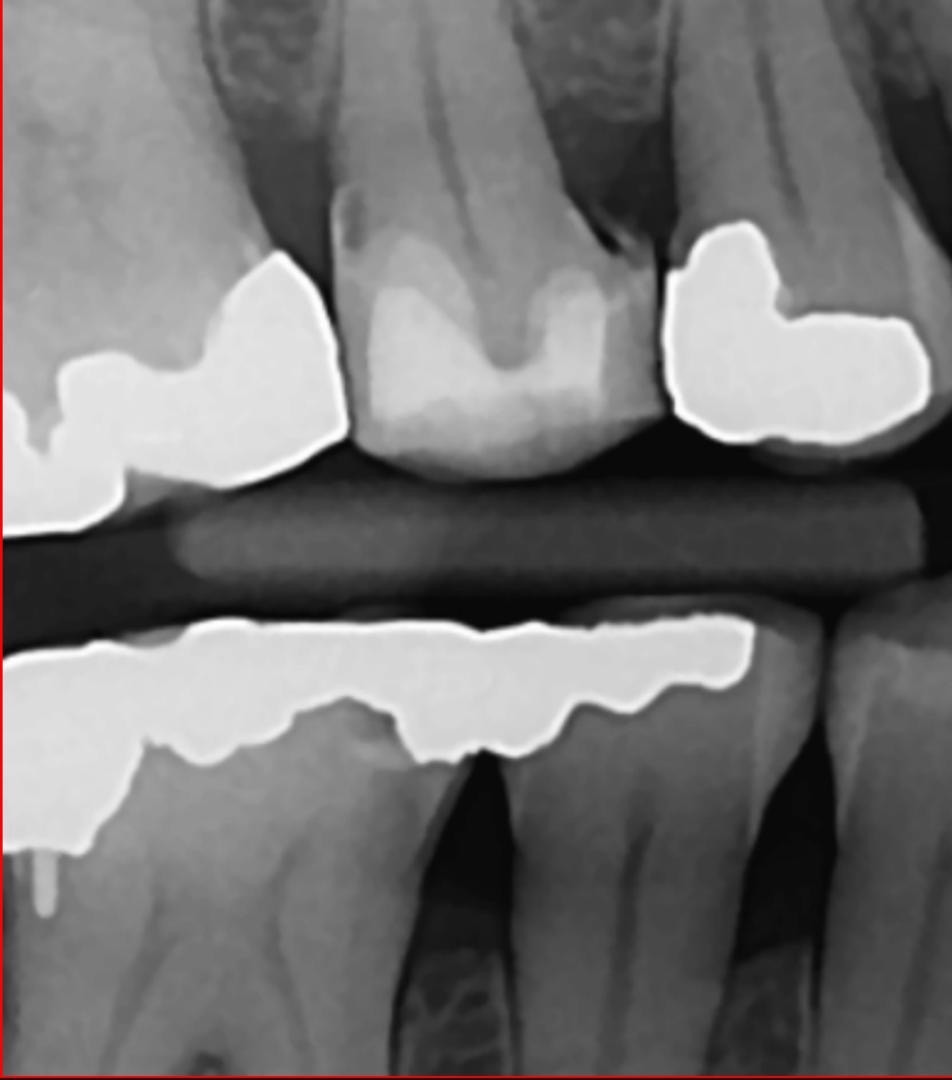

3. In the X ray bellow for which jaw periodontal bone loss is evident?